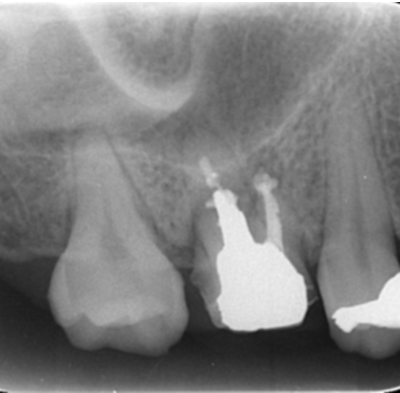

初診時デンタルX線写真

初診時デンタルX線写真とCT画像。

根管外に不透過像とそれを取り囲む透過像を認める。

コアを除去すると、分岐部へつながるパーフォレーションを認めた。

これが排膿の原因であったため、保存は困難と判断した。